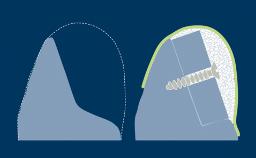

Principles of Guided Bone Regeneration (GBR)

Principles for the Management of Peri-Implant Defects

Simultaneous Contour Augmentation Using GBR